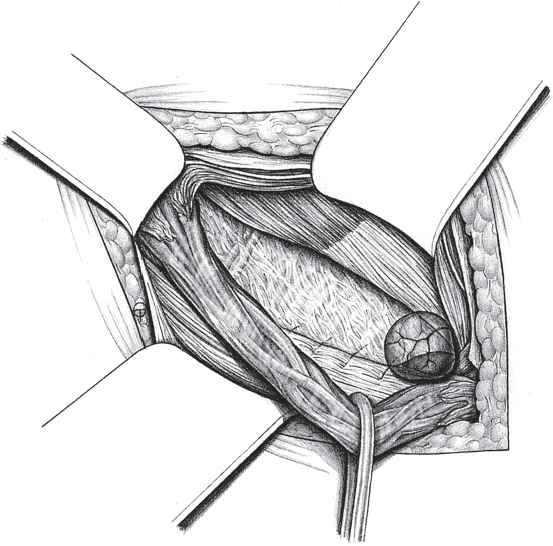

When the hernia is indirect, the sac is treated and the femoral compartment is then explored digitally through the expanded deep inguinal ring (

Fig. 3.1).